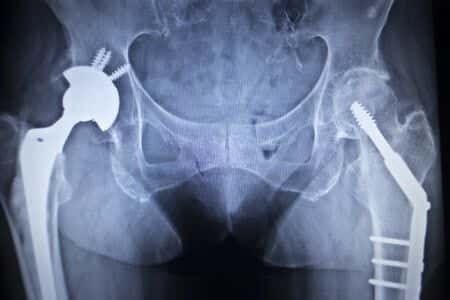

Allegedly Defective Hip Implant Causes Metallosis in Patient

This case involves an alleged defective hip implant. The plaintiff was a seventy-three-year-old female who experienced significant pain while walking. She consulted with her primary physician, who referred her to an orthopedic surgeon. The surgeon determined that a total hip replacement was required and she was scheduled for surgery. Four weeks later, the plaintiff underwent what was deemed a successful surgery. One year following the surgery, the plaintiff began feeling pain and swelling in her right hip, which resulted in difficulty walking. After two months of continual and progressive discomfort, she went back to the orthopedic surgeon to determine the cause of the pain. He determined that a significant amount of metallic debris had shed off into her body, resulting in metallosis. As a result, the plaintiff had to undergo revision surgery two weeks later to remove the implant. She likewise required long-term locomotor training in order to regain her balance and improve her movement.